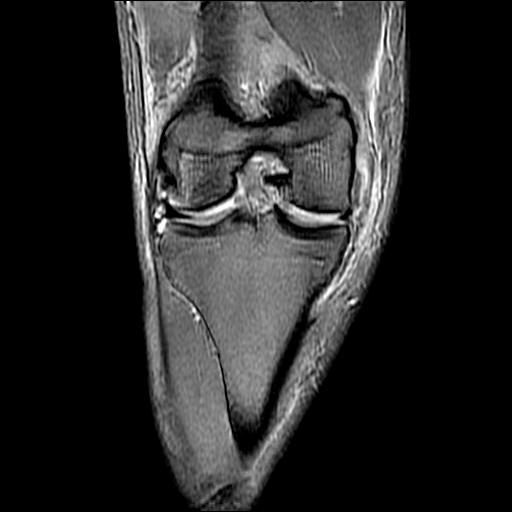

标题: MRI1265:男性40岁,右膝关节 [打印本页]

标题: MRI1265:男性40岁,右膝关节

40岁男性,右膝关节外伤,x光平片示,髁间隆突撕脱骨折。

1、前交叉韧带撕裂;

2、外侧半月板后角撕裂;

3、关节腔积液。

半月板1-2级损伤   前交叉韧带撕裂伤   关节腔少量积液  诸骨未见新鲜外伤性改变

髁间隆突撕脱骨折;内侧副韧带损伤。

1、内侧副韧带撕裂;

2、前交叉韧带撕裂;

3、滑膜炎伴关节腔积液。

1、前交叉韧、内侧副韧带撕裂;

3、关节腔积液。4、髁间脊撕脱骨折。

、内侧副韧带撕裂;

2、前交叉韧带撕裂